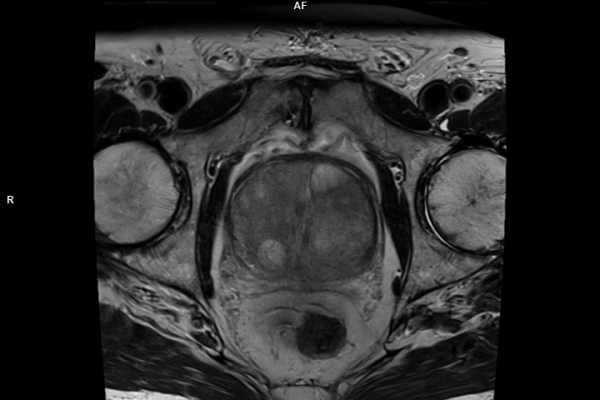

Detailbild MRT

Modernste Bildgebung für jeden Bereich Ihres Körpers

Entdecken Sie, welche CT- und MRT-Untersuchungen in unserer Radiologie für jeden Bereich Ihres Körpers möglich sind.

• Bildgebende Endometriose-Abklärung

Wir bieten ein breites Spektrum an Untersuchungen an, von Standarduntersuchungen der Gelenke, Organe oder großflächigen Körperregionen bis zu Spezialuntersuchungen zum Beispiel des Herzen oder der Gefäße. Zusätzlich werden Angiographien (Darstellung von Blutgefäßen), Endometriose-Abklärungen und Mamma-Untersuchungen durchgeführt. Genauere Details können Sie der MRT/CT-Übersicht und der Preisliste entnehmen, oder Sie wenden sich direkt an unser Team, das Sie gerne zur passenden Untersuchung berät.